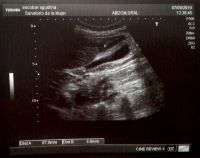

Se trató de una paciente mujer de 18 años, con diagnóstico de mononucleosis infecciosa 10 días previos a la consulta, que acudió a nuestro centro por cuadro de 48 horas de evolución caracterizado por dolor abdominal continuo, localizado en epigastrio e hipocondrio derecho, asociado a fiebre, vómitos e ictericia. Al ingreso presentaba defensa en hipocondrio derecho, leucocitos 14.960/ml; linfocitos 62%; monocitos 18%; ALT 330 U/L AST 241 U/L, FAL 125 U/L bilirrubina total 2,7 mg/dl, directa 2 mg/dl, IgM e IgG anti antígeno de cápside de VEB positivas. Resto de serologías virales negativas. Se le realizó ecografía de abdomen que evidenció vesícula biliar distendida, alitiásica, de paredes engrosadas de 6.6mm de espesor y vía biliar no dilatada. Se realizaron hemocultivos y se inició antibioticoterapia empírica cubriendo foco biliar. Evolucionó con descenso en las enzimas hepáticas y desaparición de la fiebre y vómitos. Luego de 48 horas de internación no presentaba dolor abdominal espontáneo, por lo que se reinició dieta con buena tolerancia y se suspendieron antibióticos en ausencia de rescates bacteriológicos. Se le realizó ecografía de control a las 72 horas de internación que evidenció pared vesicular de 5.1mm, tras lo cual fue dada de alta. Se controló evolución ambulatoriamente con resolución ecográfica y bioquímica ad integrum.

Figura 2: Luego de 72 hs. se realizó control ecográfico observándose vesícula alitiásica con paredes de 5.1 mm de espesor.